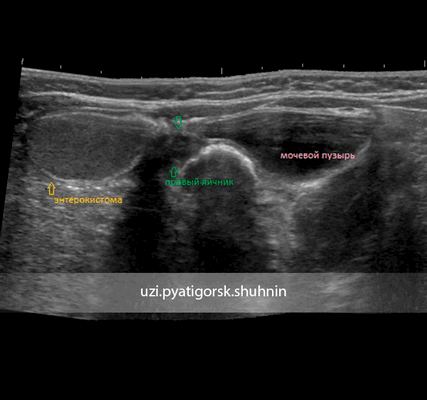

Панорамное УЗИ брюшной полости, тот же случай. Панорамное УЗИ позволяет наглядно представить взаимное расположение кистозного образования и органов брюшной полости.